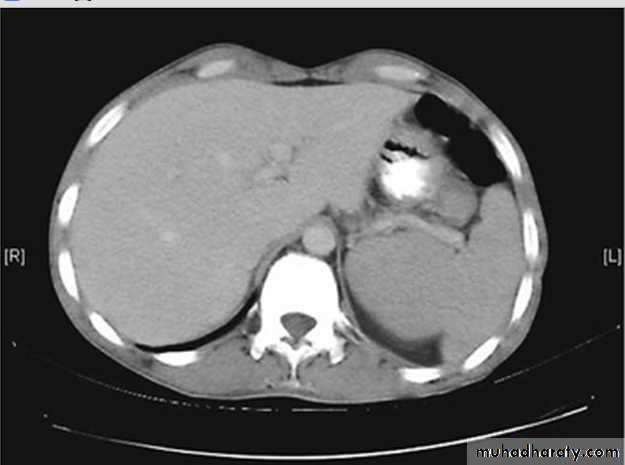

B- Radiologic features; includes U/S of abdomen with or without Doppler of the portal and hepatic venous vessels. CT or MRI; which show liver atrophy with nodular surface and features of portal hypertension.

Normal liver on CT scan, with smooth liver contours; normal size of spleen.